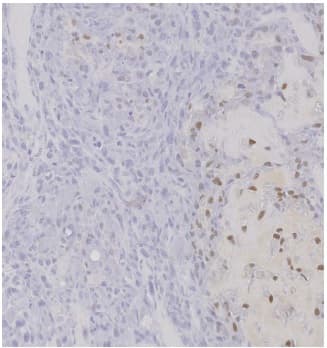

Anti-Sp7 / Osterix antibody ab22552 is a rabbit polyclonal antibody that is used in Sp7 / Osterix IHC. Suitable for mouse and rat samples.

Applications IHC-P

Species Reactivity Mouse, Rat